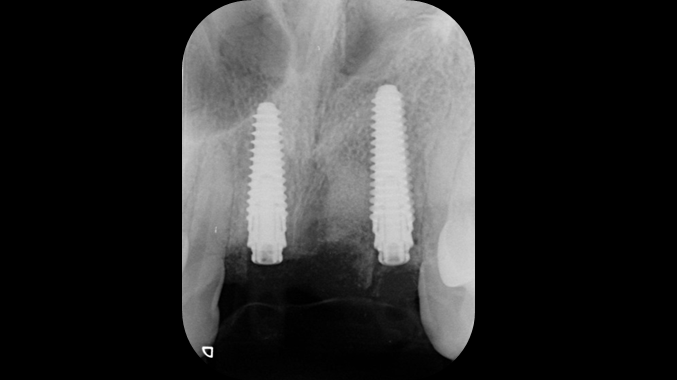

“AnyRidge is perfect for the anterior esthetic zone due to its strong initial stability & fast osseointegration.

Plus, KnifeThread® ensures space maintenance when using the PET/Socket Shield/Root Membrane Technique, showing excellent bone growth.”